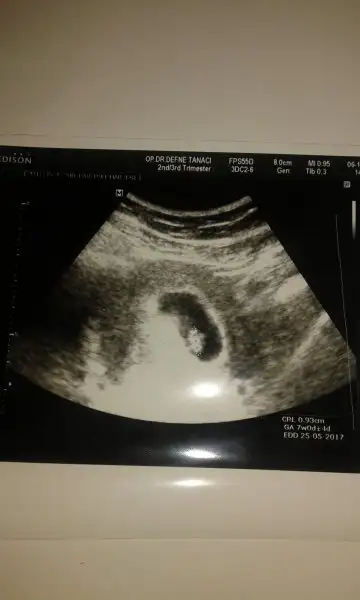

Hazirandaki gebeliğim sonlandı maalesef.pıhtılaşma olmuş ve bebeğimin kalbi durmuş.şimdi allahın izniyle tekrar hamileyim kan suşandırıcı iğne kullanıyyorum.yorum yaparmısınız usg lere.2 side karından .ilk resim 7 hafta 2.si 6+3.

Allah bağışlasın canım.evet karından,bir kızım var 7 yaşında buda 2. Miz :) kızıma kızkardeş mi erkek kardeş mi gelecek bakalım.12.haftada gideceğim tekrar belkş Dr bi tahmin yapar